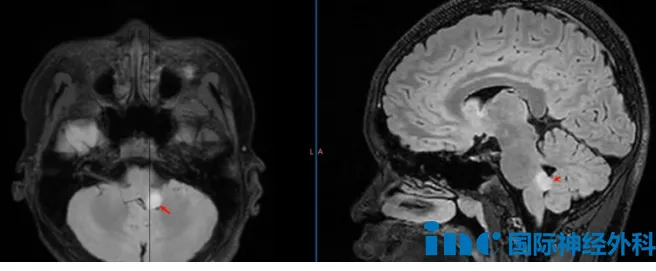

最初,只是寻常的头痛头晕——这是儿科疾病中非常常见的症状,但其背后的原因不可胜举,对应的疾病也有重有轻。比较常见的如唿吸道感染或胃肠道疾病;比较严重的就是颅内的疾病。对嘉乐而言,第一次检查发现:左桥臂有个8毫米的结节。

11月的复查结果让所有人心头一紧:病灶在半年内几乎翻倍,长至13×13×10毫米。“手术吧。”这一次,医生给出了不同的建议,但这个位置手术风险高。

巴教授评估了嘉乐的情况:从5月到11月,短短半年病变体积几乎翻了一倍。如果再等半年,它很可能再翻一倍,那样情况会更复杂。而且,过去半年病变增长得这么快,本身就说明肿瘤内部可能发生了变化,这种变化甚至可能导向恶性转化。不仅仅是体积问题,肿瘤的攻击性才是关键。